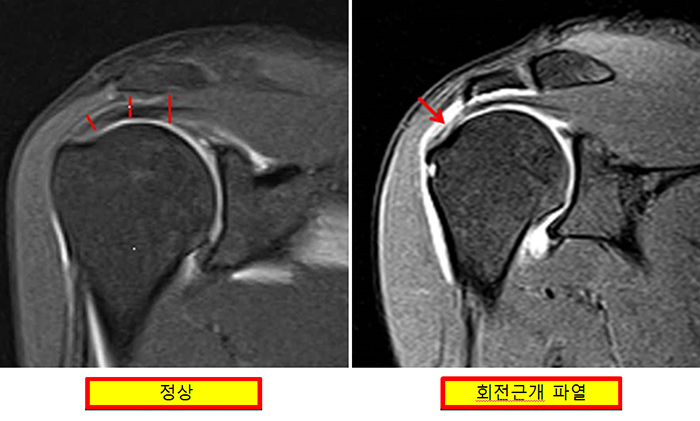

회전근개는 어깨를 움직이는 근육으로 상완골두에 붙어 상완골을 움직임으로써 어깨를 움직입니다. 회전근개의 힘줄이 지나는 공간이 다양한 원인으로 좁아지면 통증이 발생하고 좁아진 상태가 지속되면 점차 점액낭염, 회전근개 파열이 발생합니다.